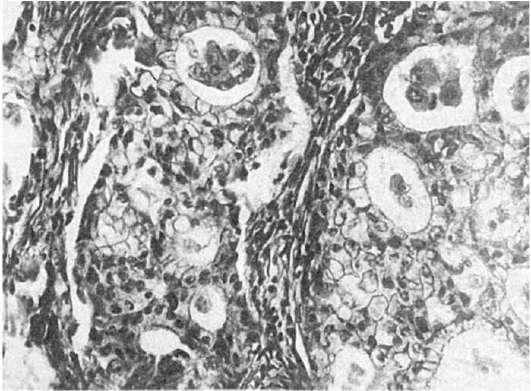

Аденокарцинома легкого также может иметь различную степень дифференцировки.Высокодифференцированная аденокарцинома состоит из ацинарных, тубулярных или сосочковых структур, клетки которых продуцируют слизь (рис. 195); умеренно дифференцированная аденокарцинома имеет железисто-солидное строение, в ней встречается большое число митозов, слизеобразование отмечается лишь у части клеток; низкодифференцированная аденокарцинома состоит из солидных структур,

полигональные клетки ее способны продуцировать слизь. Разновидность аденокарциномы -

Рис.

195. Аденокарцинома легкого, слизь в просвете ячеек железистых структур